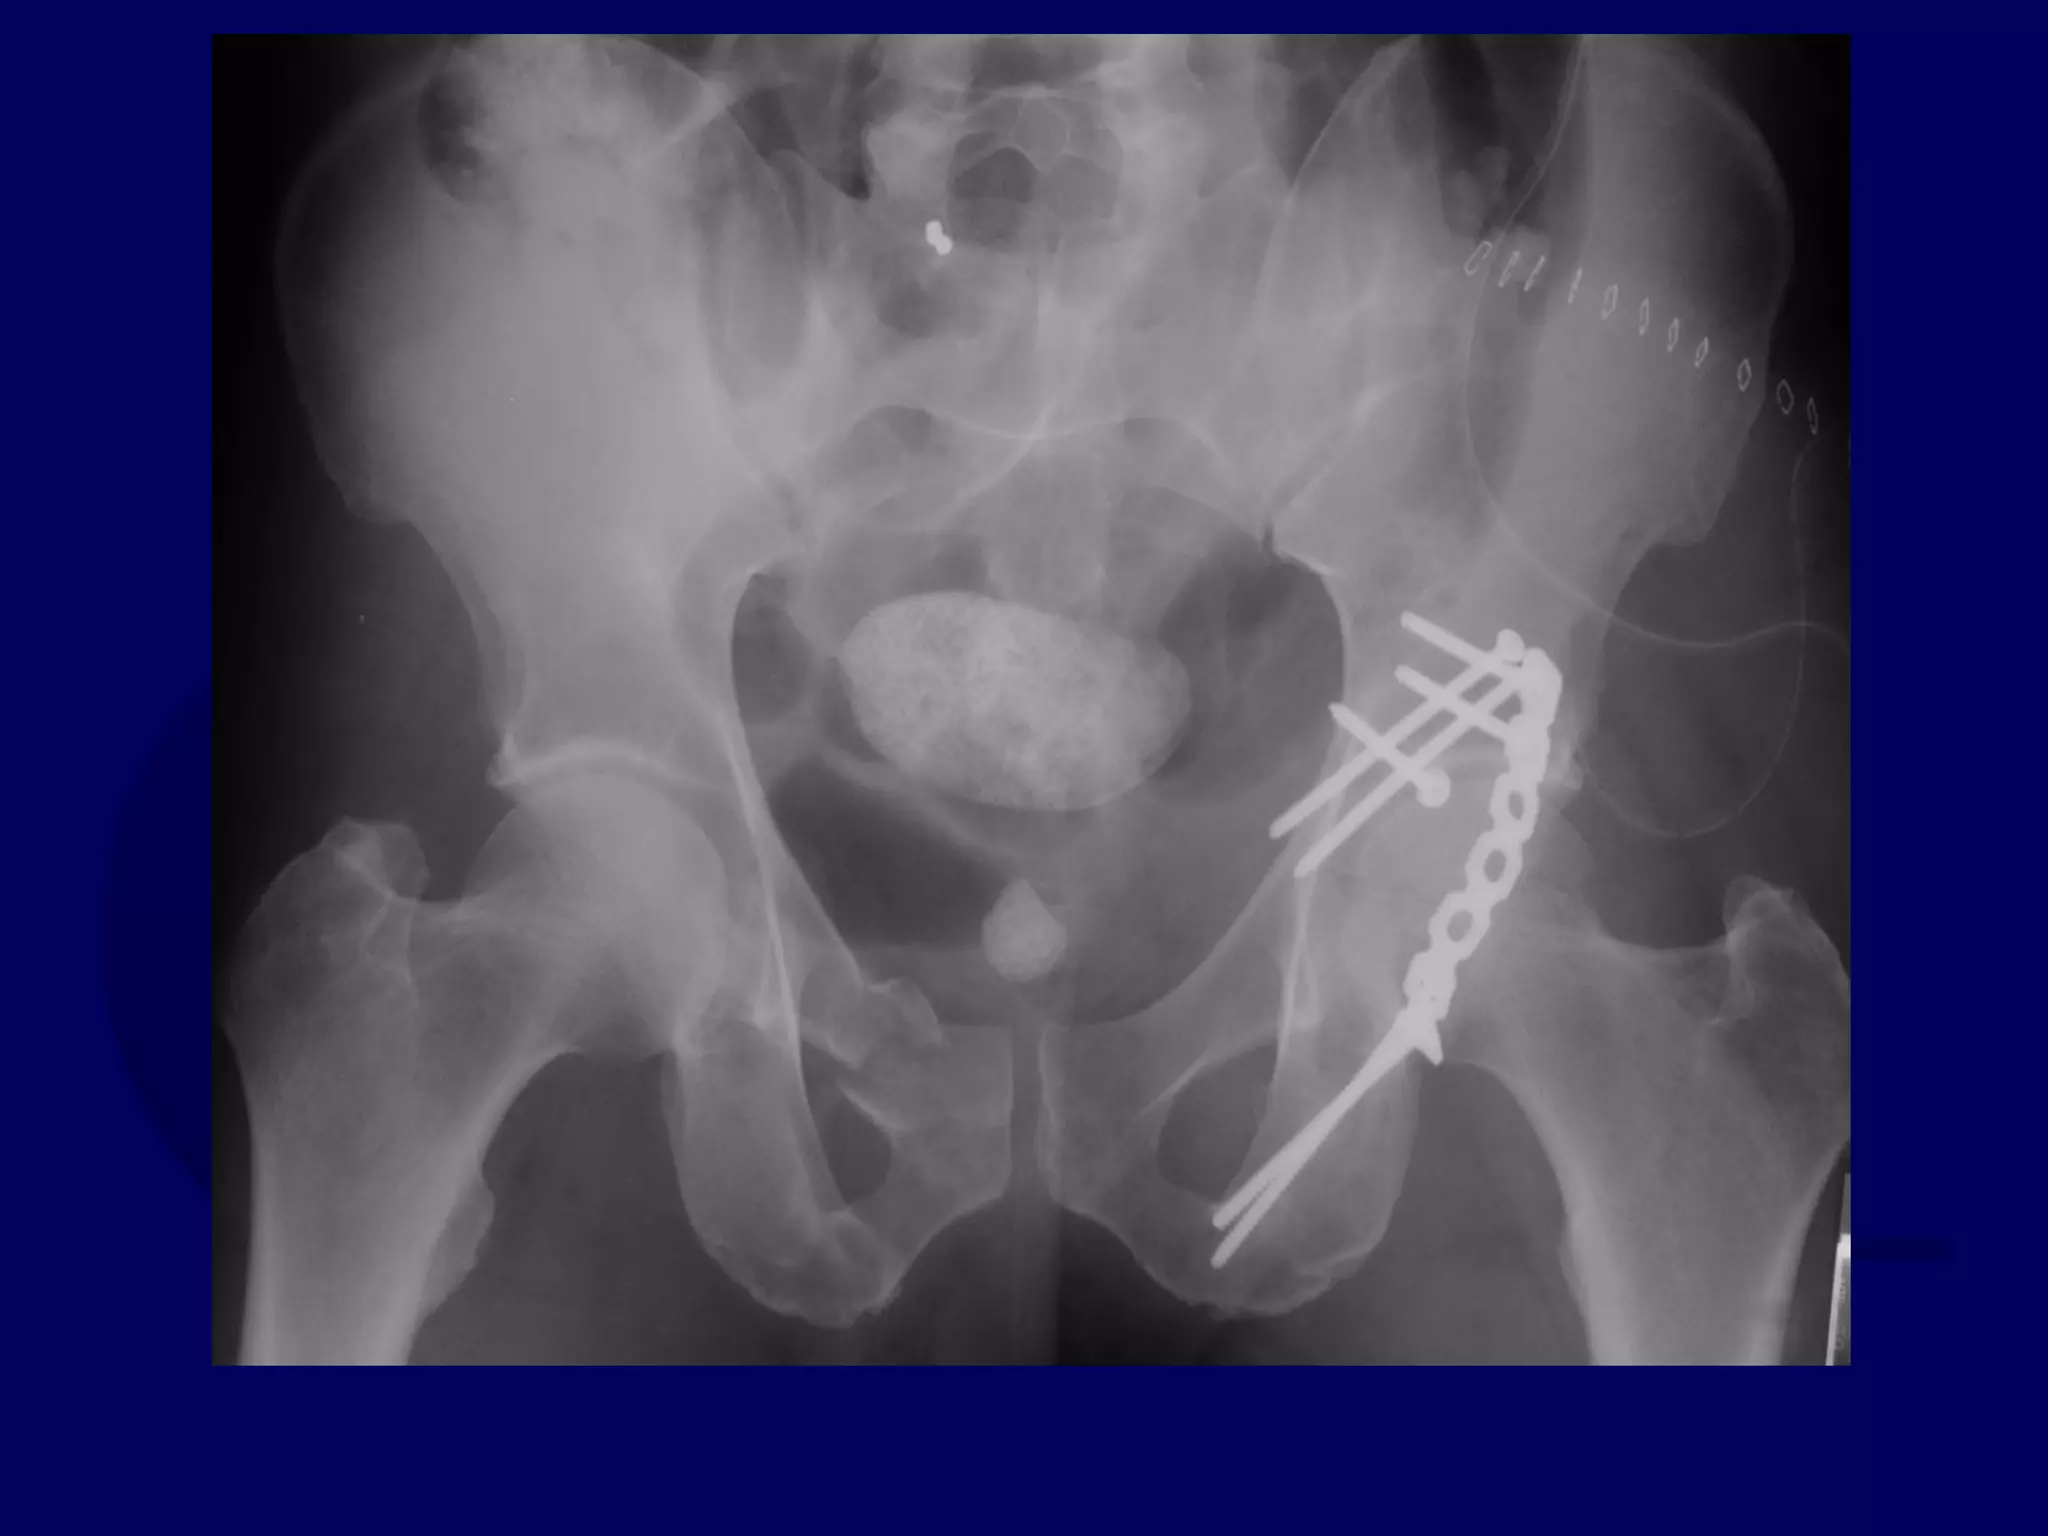

P.J. 00.12.16

Initial Kocher-Langenbeck

Approach

P.J. 00.12.18

Subsequent Ilioinguinal

P.J. 00.12.22